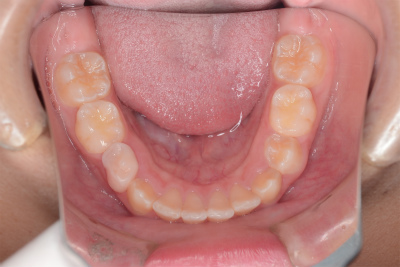

小学5年生